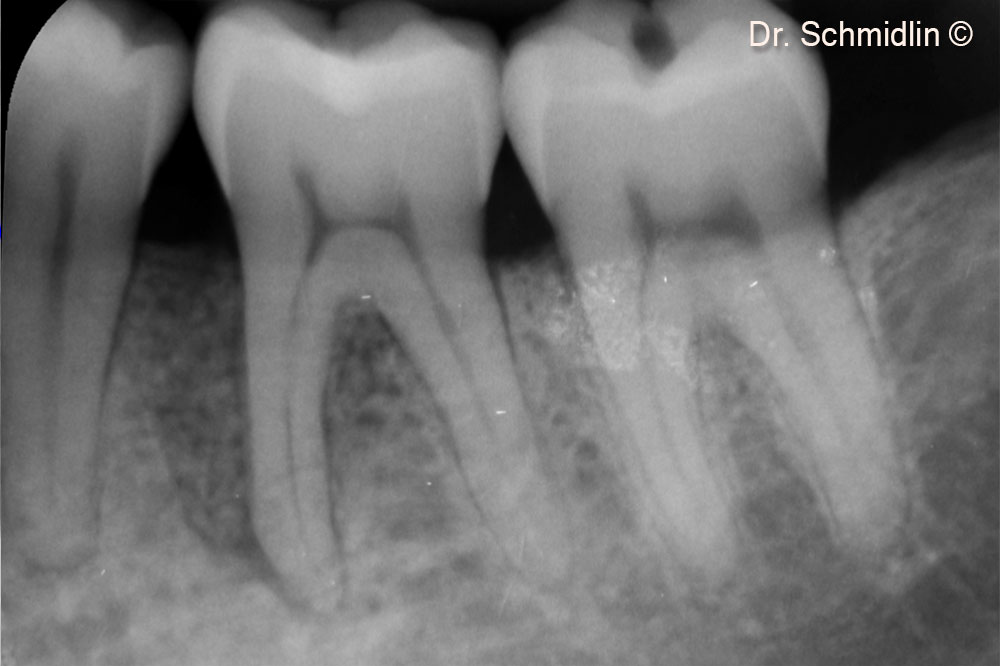

Preoperative X-ray